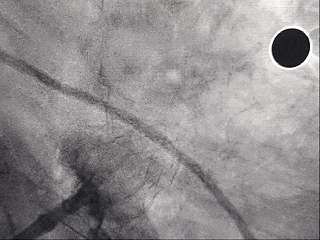

测量压缩比

右肩位下测量压缩比为10.7%

封堵合适

造影后无残余分流

封堵器完全释放

右前斜

右肩位

左前斜位

肝位

多角度观察心包积液情况,无新增心包积液,同时封堵器稳定封堵心耳口部。